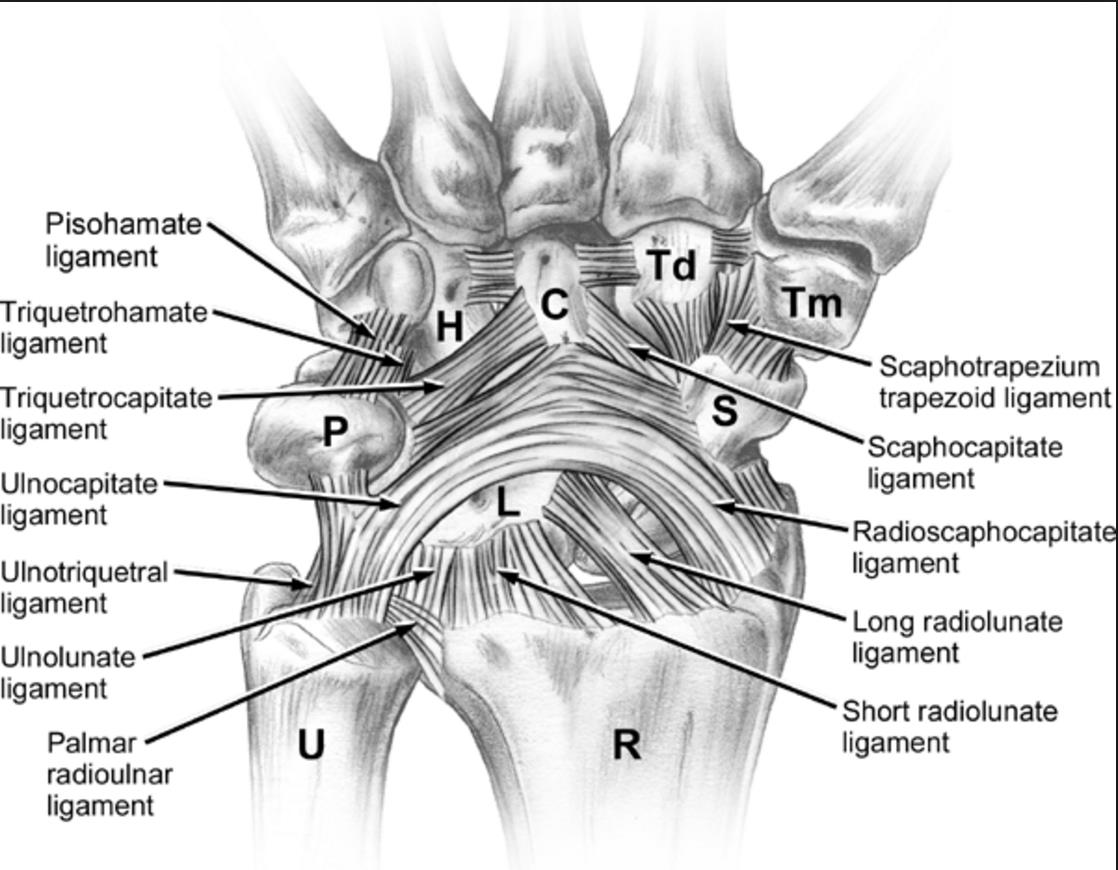

The palmar midcarpal ligaments play an important role in stabilizing the midcarpal joint by connecting the proximal and distal carpal rows. Key ligaments in this group include the scaphotrapeziotrapezoid ligament, scaphocapitate ligament, triquetrocapitate ligament, and

A TFCC tear refers to injury of the triangular fibrocartilage complex, a key stabilizer of the distal radioulnar joint and ulnar side of the wrist. Tears can occur from acute trauma, such as a fall on an outstretched hand, or from chronic repetitive loading, particularly with